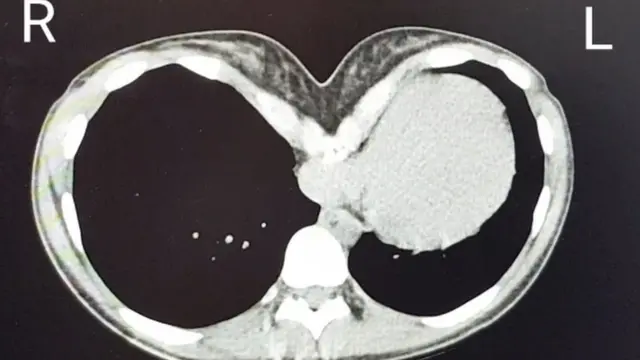

Padece el síndrome del pecho hundido, una condición médica rara que, en muchos casos, provoca una malformación de la pared torácica causada por el hundimiento del esternón.

Dicho de otra forma, es una enfermedad que puede aplastar el corazón a quien la sufre.

Según la Clínica Mayo, si bien en algunos casos el único síntoma es la deformidad del pecho, en los más graves el esternón puede comprimir los pulmones y el corazón.

"Ella nunca ha sabido cómo es ser normal", dice Dunning, quien agrega que "sin duda" el corazón de su paciente está siendo "aplastado" por su esternón.